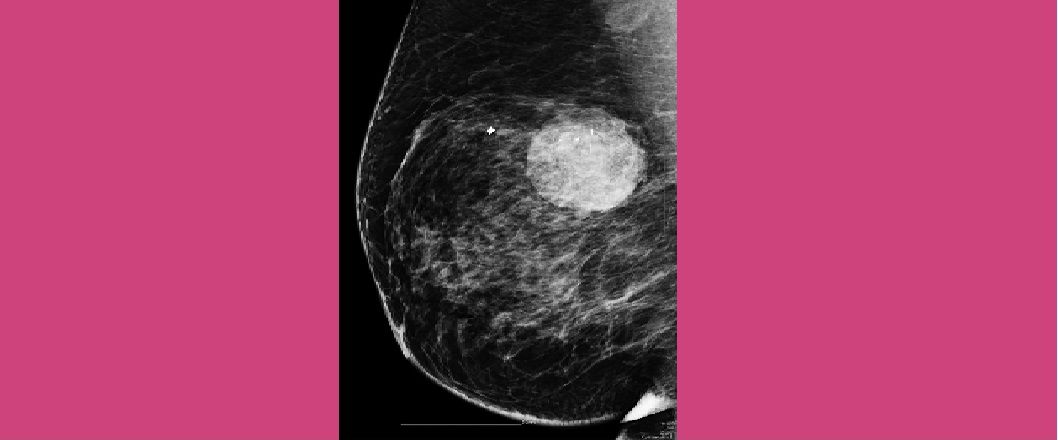

Διάγνωση Ογκιδίου Μαστού

09.Δεκ.2021

Βασίλειος Καλλές